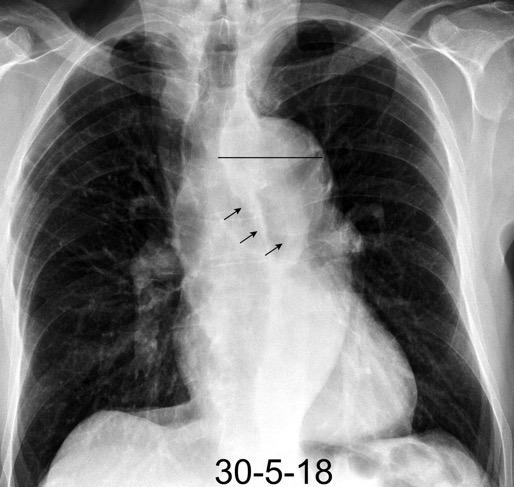

Hodgkin clásico de esclerosis nodular.

Adenopatías región cervical y mamaria interna, prevasculares y VAP. Doble contorno aórtico.